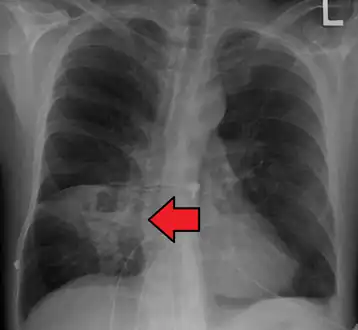

Pulmonary abscess on CXR

Lung abscesses are often on one side and single involving posterior segments of the upper lobes and the apical segments of the lower lobes as these areas are gravity dependent when lying down. Presence of air-fluid levels implies rupture into the bronchial tree or rarely growth of gas forming organism.

a,b)Hollow lesion in the lower left lung field was diagnosed as a lung abscess